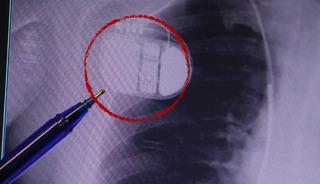

2 Kasım Pazar günü VF-90 koduyla Köln-İstanbul seferini yapan uçakta, Sabiha Gökçen Havalimanı’na inişine kısa süre kala teknik bir problem meydana geldiğini belirten Yeşilkaya şunları ifade etti:

"Gerekli prosedürler uygulanarak, misafirlerimize uçuş emniyeti çerçevesinde bilgilendirme yapılmıştır. Uçağımız emniyetli bir şekilde inişini gerçekleştirmiş ve herhangi bir sorun yaşanmadan seferini tamamlamıştır. Kamuoyuna saygı ile duyurulur.”